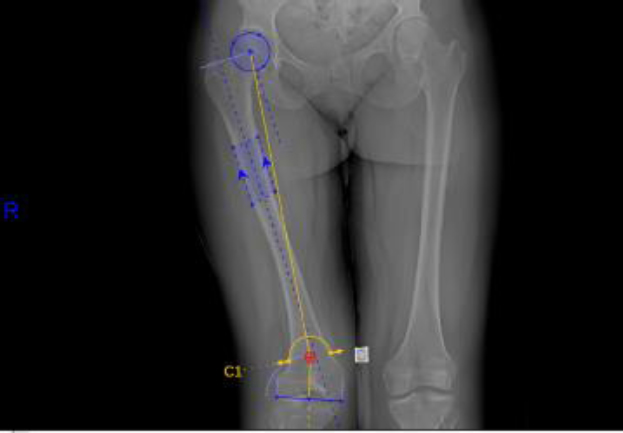

Identifying the proper osteotomy site requires an understanding of the three-dimensional structure of the bone contributing to the deformity, as well as the correction required to restore alignment of the patient’s innate mechanical axis. The pre-operative MAD is measured with bilateral standing hip-to-ankle films with a plumbline connecting the center of the hip to the center of the talus. The MAD is measured from the center of the knee to the mechanical axis line (Fig. 1). Varus deformities have a positive MAD, while valgus deformities have a negative MAD. Joint centers are identified at the hip, knee, and ankle, and the mechanical axes and joint lines are then drawn. This information will determine the joint angles, comparing them to population norm measurements. After analyzing the joint angles, the deformity is identified at either the femur, tibia, or both. The apex of the deformity is identified, which often dictates the location of the planned osteotomy (Fig. 2). Occasionally, the apex of the lower limb deformity is at the knee joint, which requires an alternative location for the osteotomy at the expense of accepting translation after DC. In patients with clinical symptoms and radiographic evidence of unicompartmental osteoarthritis, targeted deformity correction was templated to over-correct for this deformity. Additionally, in 1 patient (patient #18), a postoperative valgus alignment was planned to restore metadiaphyseal alignment for subsequent placement of knee arthroplasty components. As a result, correction of MAD from the preoperative to postoperative state is also reported with targeted/goal correction, as not all patients’ MADs were targeted to 0 mm.

Preoperative analysis of the mechanical axis depicts 40 mm of lateral joint deviation in a patient with right femoral valgus (patient #14). The red dashed line represents the mechanical axis. Lateral distal femoral angle (77°) and medial proximal tibial angle (90.5°) are also shown for reference.

Preoperative hip-to-ankle standing radiograph with templated dome osteotomy for correction of a femoral deformity (patient #14).